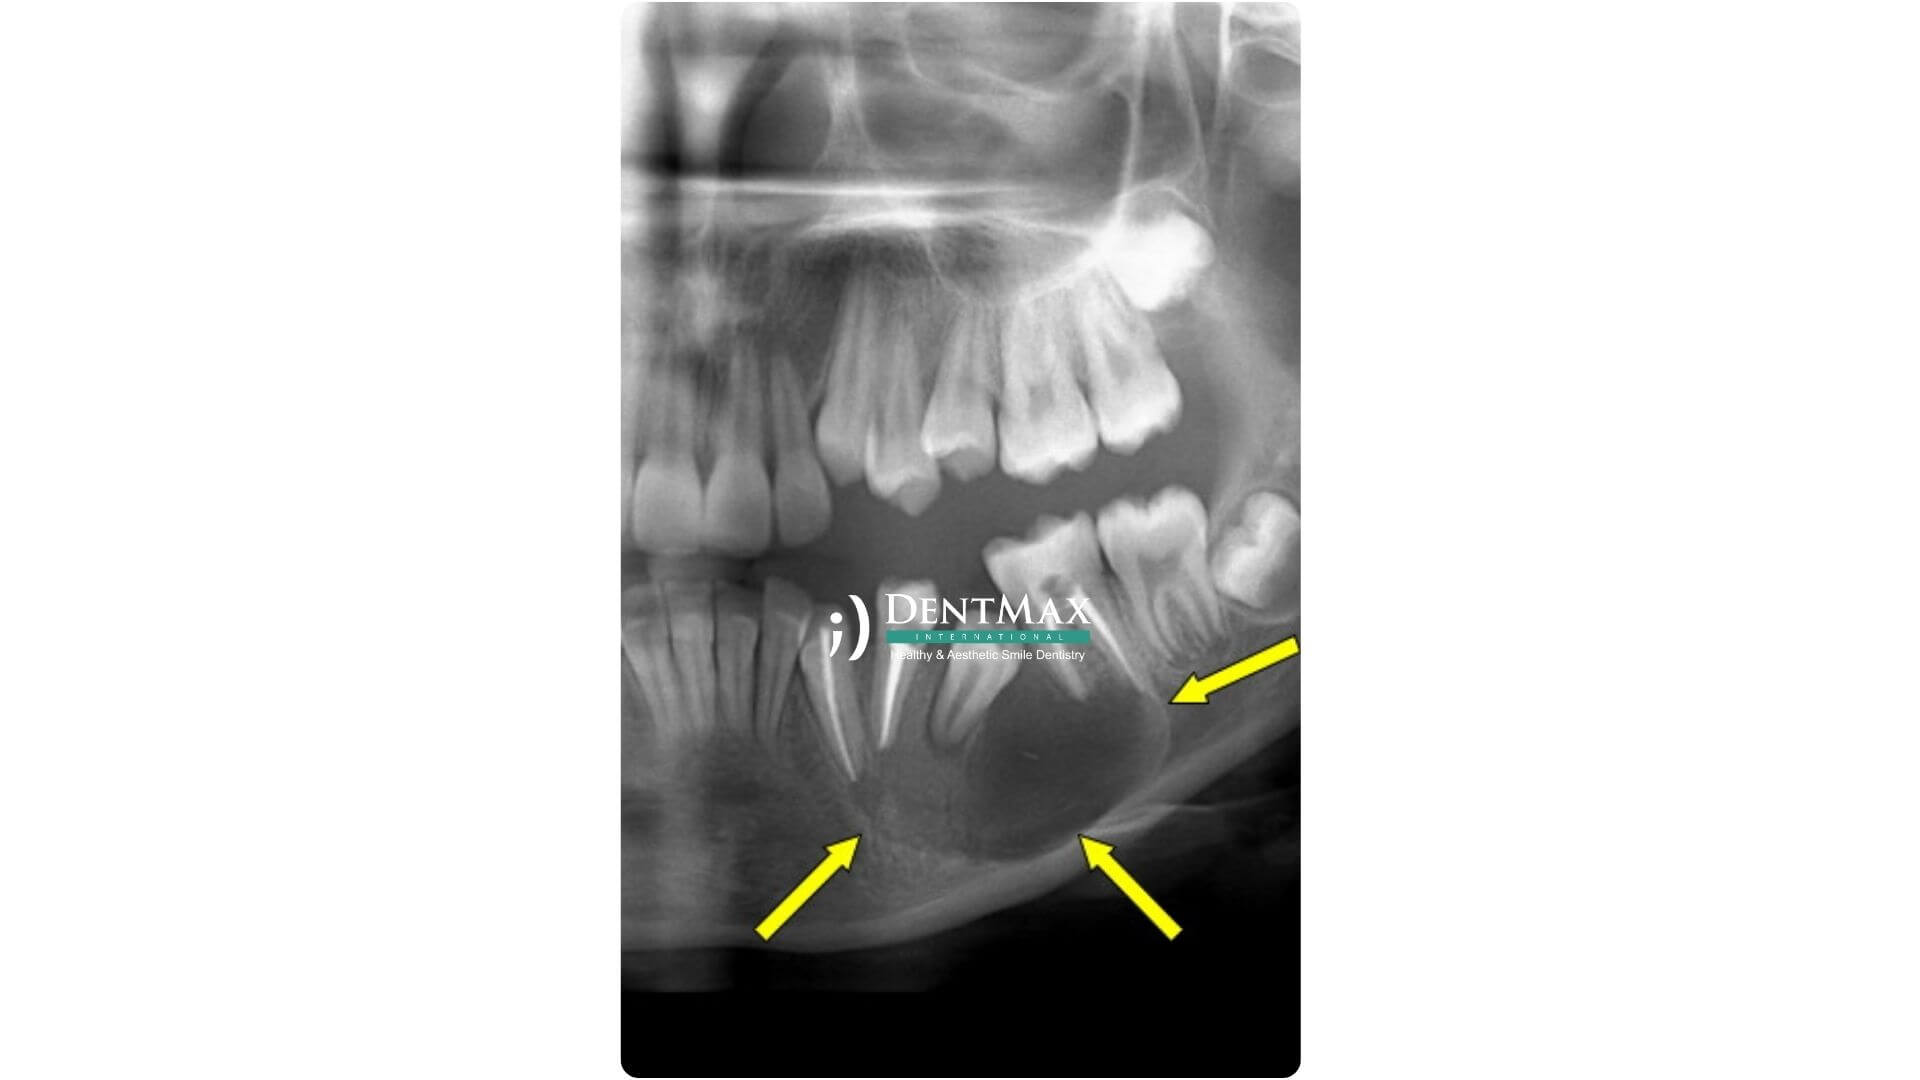

Çene kisti, genellikle enfeksiyon, gömülü dişler veya travma nedeniyle çene kemiği içinde sıvı dolu boşluklar şeklinde oluşan patolojik yapılardır. Belirtileri arasında ağrı, şişlik, dişlerde gevşeme veya çene kemiğinde incelme görülebilir. Erken teşhis, diş ve çene yapısının korunması açısından büyük önem taşır.

1. Aşama – Teşhis ve Görüntüleme

Öncelikle dental tomografi (CBCT) çekilerek kistin boyutu, konumu ve çevre dokularla ilişkisi değerlendirilir.

Panoramik röntgen ve klinik muayene sonucunda kistin türü belirlenir.

Dental tomografi (CBCT), panoramik röntgen ve gerektiğinde iMetric 4D ölçüm sistemi kullanılır.